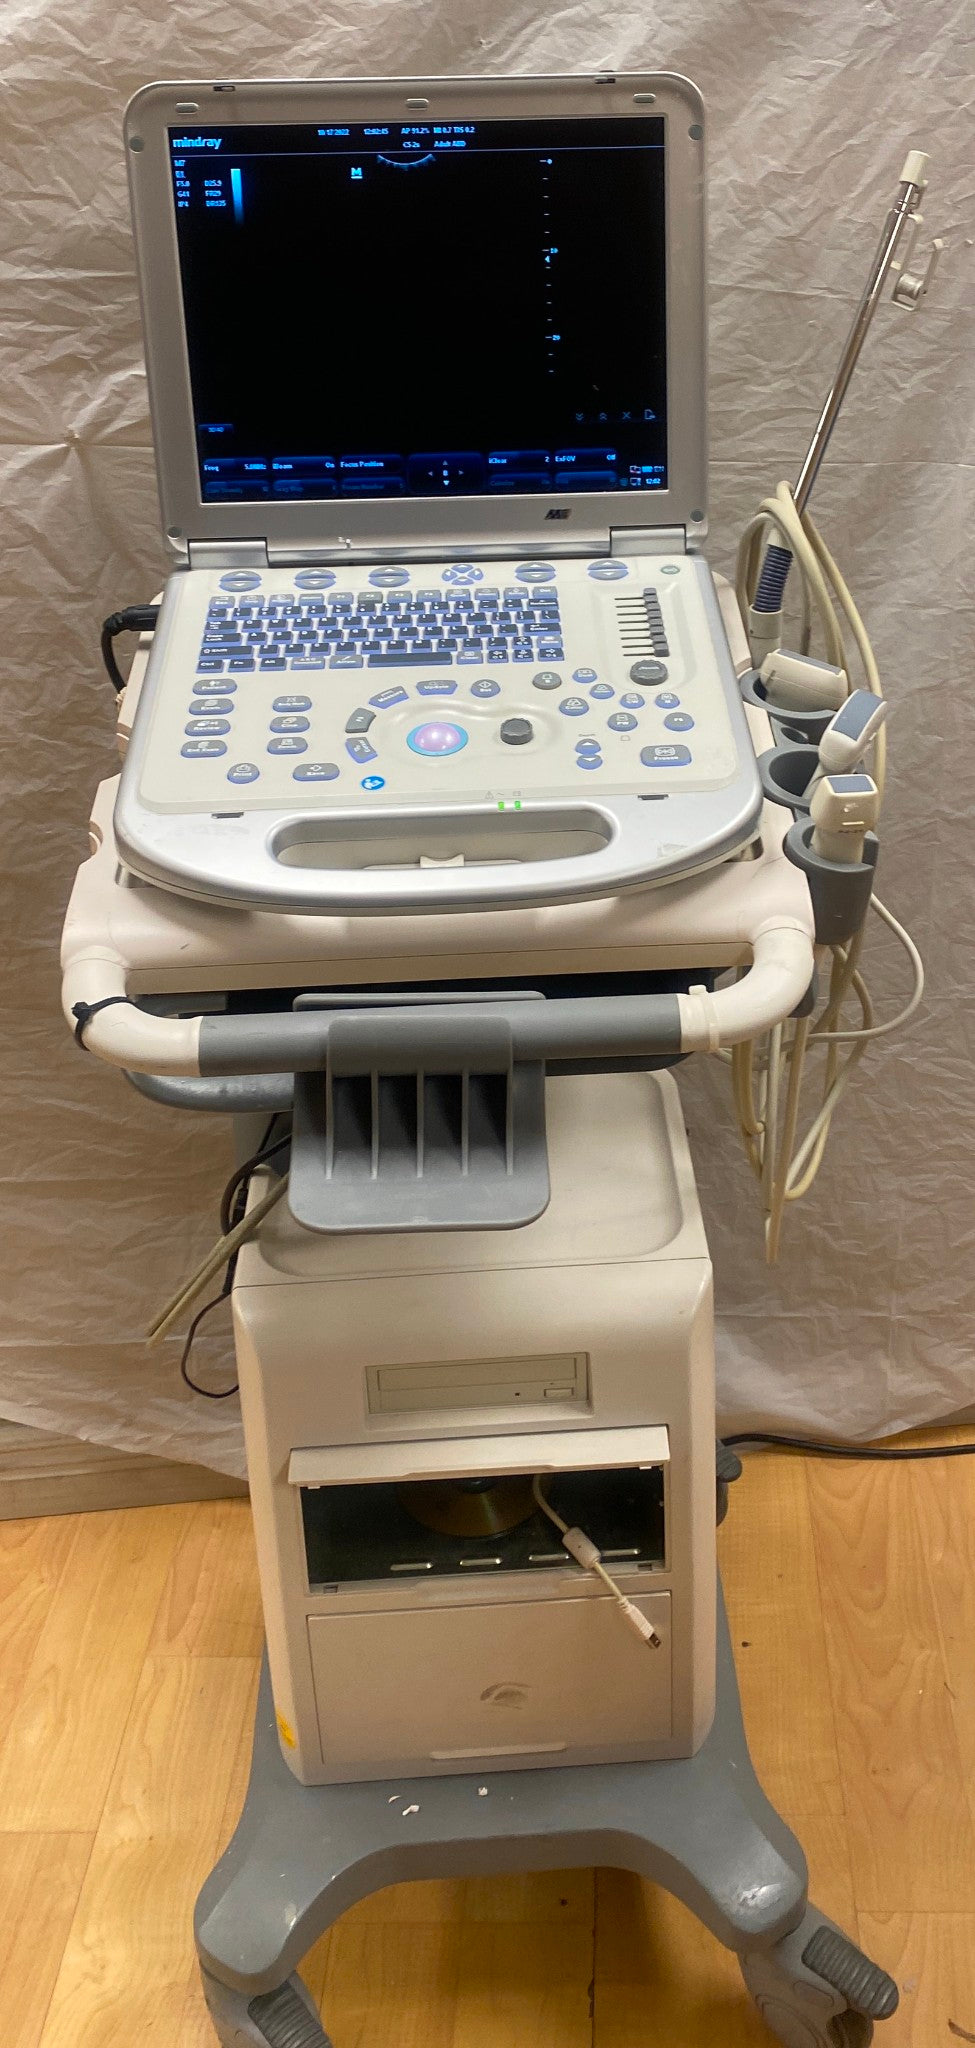

DIAGNOSTIC ULTRASOUND MACHINES FOR SALE

Mindray M9 Portable Ultrasound With 2 Probes

Sale price$ 22,302.88